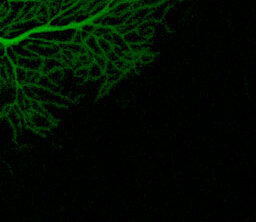

Фото: Клетка Пуркинье Wikimedia CommonsКлетка Пуркинье Wikimedia Commons

Проведя электрофизиологические исследования отдельных нейронов in vivo, ученые смогли показать, что гипоксия нарушает работу огромных нейронов Пуркинье – больших ветвистых клеток коры мозжечка, которые замедляют частоту нервных импульсов. Это помогло подобрать терапию – препарат, который поднимает уровень гамма-аминомасляной кислоты (ГАМК), нейромедиатора клеток Пуркинье. Она работает возбуждающим нейромедиатором до и вскоре после рождения, но затем «переключается» на тормозящий эффект. Поэтому ГАМК нужно вводить сразу после гипоксии.